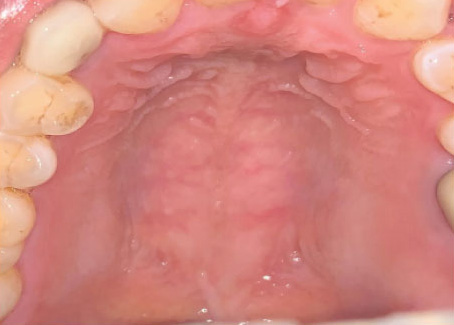

OM initially presents as erythema, with time to onset ranging from two to three weeks and one to two weeks, respectively, after initiation of HNR or CT, and from 3 to 4 days after the first treatment in conditioning regimens.6Brown TJ, Gupta A. Management of Cancer Therapy-Associated Oral Mucositis. JCO Oncol Pract 2020;16(3):103-9. While the mucosal inflammation can remain mild, OM typically develops further to an erosive phase and ulcerative lesions with pseudomembranous surfaces.1Sonis ST. Pathobiology of oral mucositis: novel insights and opportunities. J Support Oncol 2007;5(9 Suppl 4):3-11.,9Haverman TM, Raber-Durlacher JE, Rademacher WM et al. Oral complications in hematopoietic stem cell recipients: the role of inflammation. Mediators Inflamm 2014:378281. doi: 10.1155/2014/378281. When extensive, these lesions cause severe pain and can cause bleeding. OM development begins with the death of basal epithelial cells, which ensues rapidly once HNR or CT commences.1Sonis ST. Pathobiology of oral mucositis: novel insights and opportunities. J Support Oncol 2007;5(9 Suppl 4):3-11. The inflammatory process then involves the release of reactive oxygen species, gene expression and upregulation of multiple inflammatory pathways, and increased production of pro-inflammatory cytokines and other mediators.11Sonis ST, Elting LS, Keefe D et al. Mucositis Study Section of the Multinational Association for Supportive Care in Cancer. International Society for Oral Oncology. Perspectives on cancer therapy-induced mucosal injury: pathogenesis, measurement, epidemiology, and consequences for patients. Cancer 2004;100(Suppl 9):1995-2025.,12Logan RM, Stringer AM, Bowen JM et al. Serum levels of NFkappaB and pro-inflammatory cytokines following administration of mucotoxic drugs. Cancer Biol Ther 2008;77:1139-45. OM lesions typically resolve two to four weeks after cancer therapy is completed. (Figure 1)

Figure 1. OM in patients who received HNR, showing normal, moderate delayed and severe delayed healing (left to right)

Source: Jiang R, Liu Y, Zhang H et al. Distinctive microbiota of delayed healing of oral mucositis after radiotherapy of nasopharyngeal carcinoma. Front Cell Infect Microbiol 2022;12:1070322. Copyright © 2022 Jiang, Liu, Zhang, Chen, Liu, Zeng, Nie, Chen and Tan.